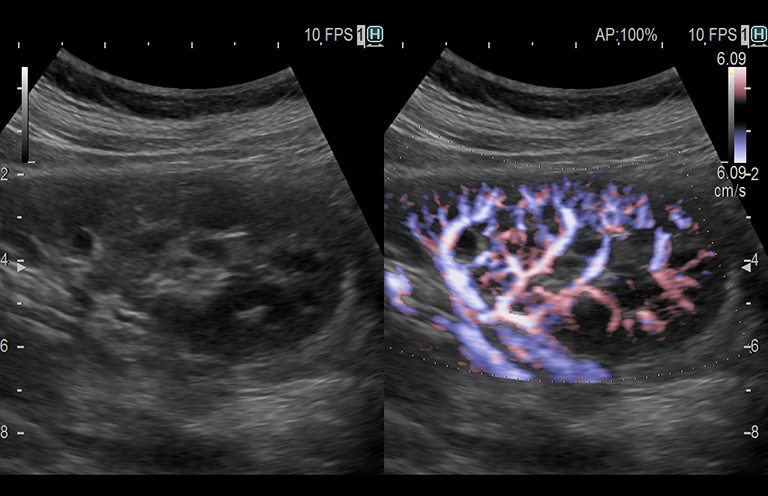

Aplicación: Abdomen

Función/Análisis: eFLOW (CF doble)

Comentarios: Riñón